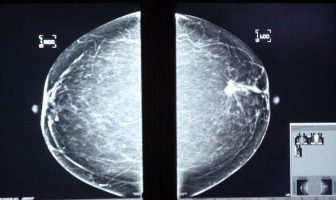

Donación Harp-Arronte vs el cáncer por 83 mdp

Las Fundaciones Alfredo Harp y Gonzalo Río Arronte, donarán a la Secretaría de Salud, sofisticados equipos para detección y tratamiento de la enfermedad, con valor…